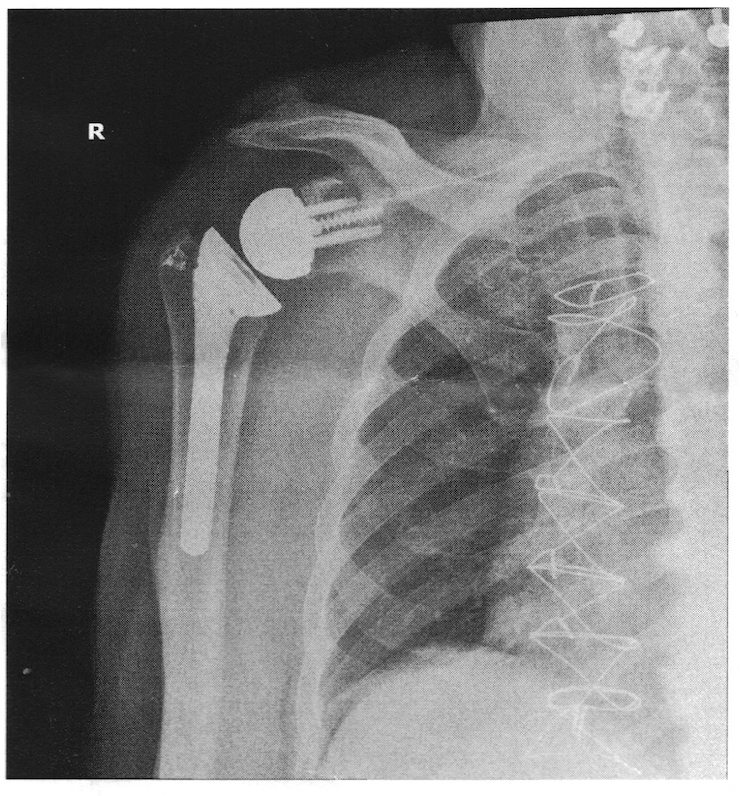

For the last two ski seasons my right shoulder has been giving me increased trouble when poling, especially in the flats. I visited my orthopedist, and x-rays revealed my shoulder had inoperable bone spurs. I needed a total shoulder joint replacement. This would be my 11th surgery in 20 years. Mentally, I wasn’t ready for another surgical procedure and stint at rehab. I inquired what my options were short of surgery. For the next two years I received quarterly cortisone shots in the shoulder. While effective over that period, last season the shots were no longer providing much pain relief, as predicted by my physician. It was time for the replacement surgery.

The new reverse joint replacement